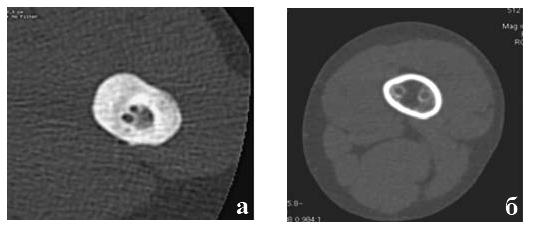

Рентгенологический контроль процесса репаративной регенерации в зоне перелома осуществляли через 2-3 недели после операции, а затем ежемесячно с помощью стандартной рентгенаппаратуры, например, ренгггенаппарат Flexavision фирмы Shimadsu, а после демонтажа аппарата Илизарова и удаления интрамедуллярных спиц, через 6-12 месяцев, на мультиспиральном компьютерном томографе Light Speed VCT GE (MCKT). Исследование проводили в положении больного лежа на спине в режиме спирального сканирования с шагом томографирования 1 мм и минимальной толщиной среза 0,7 мм. Протокол исследования Extremity (knee). Зона интереса определялась по обзорной томограмме. На полученных изображениях в интерактивном режиме выделяли область, в которой автоматически высчитывалась площадь (см2) и плотность области интереса в единицах Хаунефилда (HU).

Через 6 месяцев интрамедуллярные спицы были удалены. При томографическом исследовании определяется полное сращение костных фрагментов (Рис. 6а). На уровне перелома плотность сформированного регенерата практически соответствует плотности кортикальной пластинки бедра (1351 HU или 85 % от плотности кортикальной пластинки здорового бедра). Толщина кортикальной пластинки значительно больше, чем на здоровом бедре на том же уровне (6,2 мм против 4 мм).

Интрамедуллярные спицы располагались практически по центру костно-мозгового канала и вокруг них сформировался плотный костный футляр толщиной 1,2-1,7 мм и этот футляр окружен плотной (650 HU) массой костной ткани, которая связывала спицы с эндостом.

Подобная картина формирования костного футляра вокруг спиц наблюдается на всем их протяжении. На рис. 6б показан дистальный срез бедра на удалении от уровня перелома 8 см, где тоже видна выраженная регенерация костной ткани в виде плотного ободка вокруг интрамедуллярных спиц. Плотность этого кольца соответствует 600 едН, что соответствует 37% от уровня плотности кортикального слоя бедренной кости, а толщина 1,2-1,3 мм. Вокруг костного «футляра» отчетливо виден сектор костно-мозгового канала (более 180°) занятый плотной тканью (200 HU), который

мы расцениваем как вновь образованное губчатое костное вещество, жестко связывающее спицы с эндостом. Да и плотность оставшейся части костного мозга (по центру) выше, чем плотность костного мозга здоровой ноги (-45 HU против -65 HU).

Рис.6. Томограмма бедра пациентки К. на уровне консолидированного перелома (а) и на 8 см дистальнее (б).